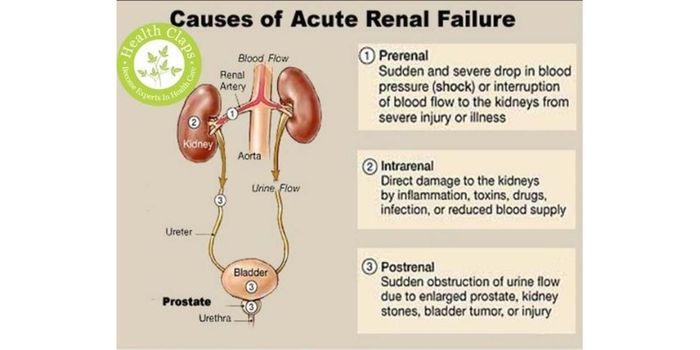

JAN 19, 2019Health & MedicineAcute kidney injury, also known as acute renal failure, involves a rapid decrease in renal function demonstrated by a re ...